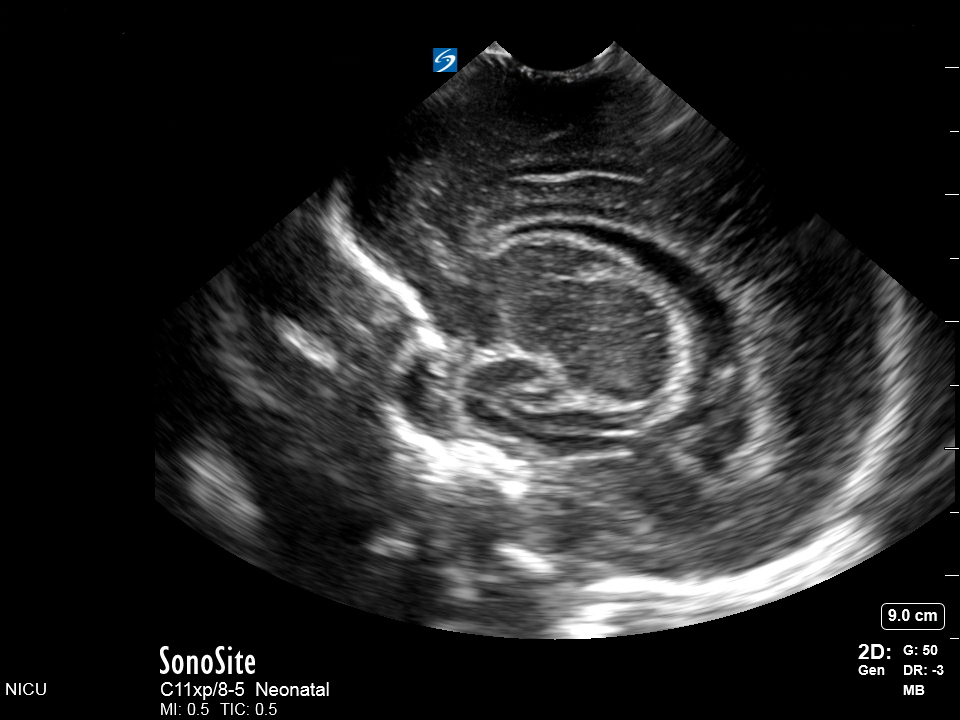

Neonatology Parasagittal Post-Hemorrhagic Ventricular Wall Thickening Image